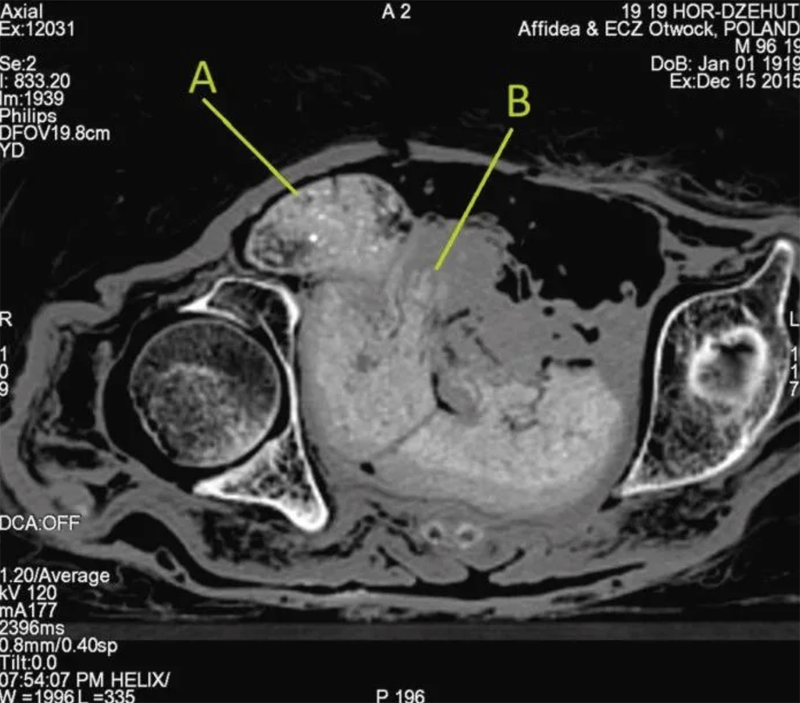

▼這具木乃伊死時的年齡在20到30歲之間,已經懷孕26到30週。更奇妙的是,木乃伊體內的胎兒在2000年後的現在,仍能保持完整。

▼研究團隊表示,木乃伊的製作方式,導致子宮成為了低氧環境,隨著遺體的血液pH值下降,再加上子宮內容物的分解,內部的酸性愈來愈高。研究團隊比喻說,胎兒就像被「醃製」一般。

▼木乃伊體內的胎兒外表保存良好,但骨頭幾乎完全消失了。科學家認為,這也是子宮內的高酸性環境導致的,胎兒的骨骼才會出現「脫礦」現象。胎兒在木乃伊的子宮內,就像將遺體放入沼澤中保存一般。